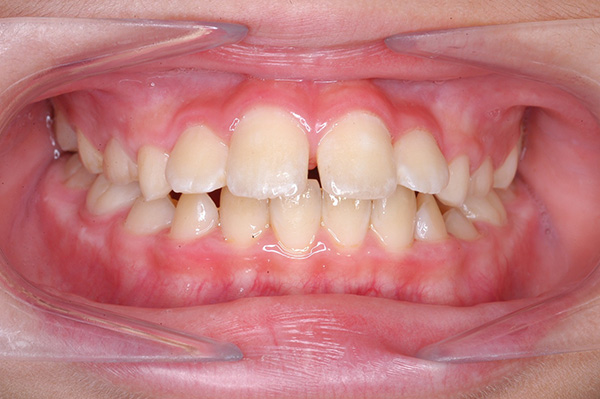

| 顔貌所見 | 正貌はほぼ左右対称。側貌はconvex type、口唇閉鎖不全、口元の突出感が認められた。 |

| 口腔内所見 | over jet 5.5mm,over bite 5.0mm,大臼歯関係はⅠ級 、Hellmanのdental ageはⅢBであり上突歯列を呈していた。 |